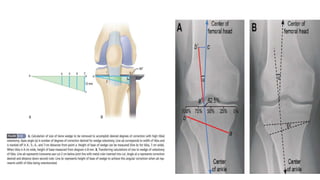

Knee adduction moment (KAM) during gait is known to indicate disease severity and prognosis of

varus knee Thus, to reduce KAM is a key strategy in treatment of knee OA.

KAM is primarily calculated as the product of the resultant ground reaction force (GRF) in the frontal

plane and the perpendicular distance from the GRF to the knee joint center (frontal plane lever arm).